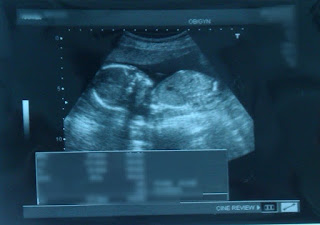

柯醫師首先會做超音波檢查,例如頭圍、肚子橫切面、脊椎、手腳、大腿骨長度確認週數...等,然後也會附贈性別說明

*摘錄自攝影片,解析度不佳。